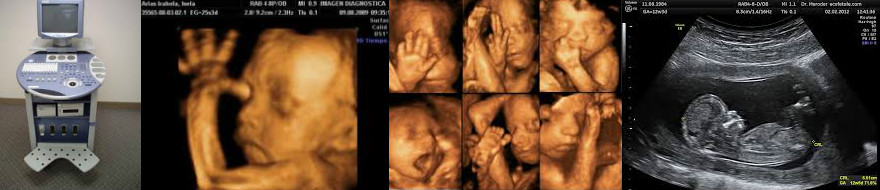

Otra muy importante es hacer imagenes del interior del cuerpo humano usando ultrasonido. Esta aplicacion usa que la energia sonora y es absorbida en forma distinta por objetos de distinta dureza por ejemplo (como los huesos y los tejidos). Lo transmitido tiene por tanto una "sombra" que permite hacer una imagen de los organos que mas absorben la energía sonora.